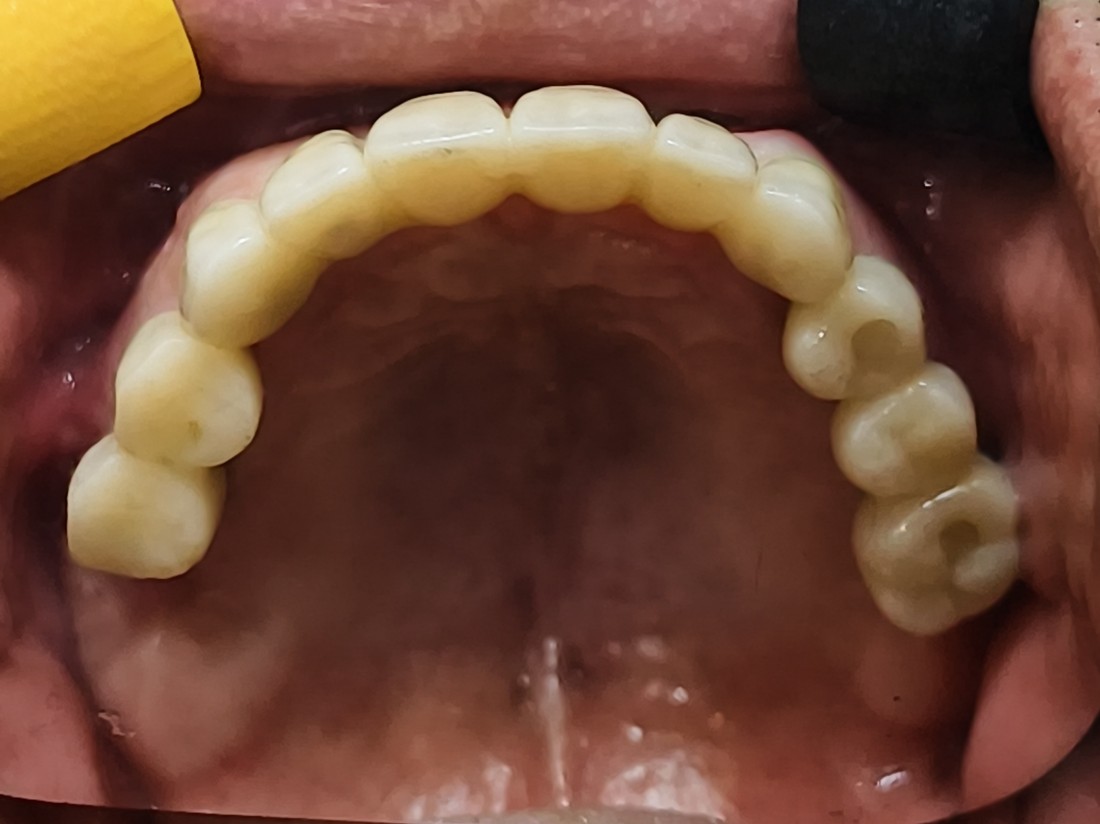

광주 전체임플란트 치과는

디지털가이드 임플란트 방식으로

한 번에 8개 이상의 임플란트를

동시에 식립할 수 있어

단 두 번의 수술만으로 전체임플란트를 완성합니다.

디지털 구강스캐너를 활용하여

치아 잇본뜨는 과정을 빠르고 정확하게 합니다.

뿐만 아니라, 자체 치아기공소를 운영하여

개인별 1:1 맞춤 최적의 보철물 제작으로

예쁘고 잘 씹어지는 임플란트를 완성합니다.